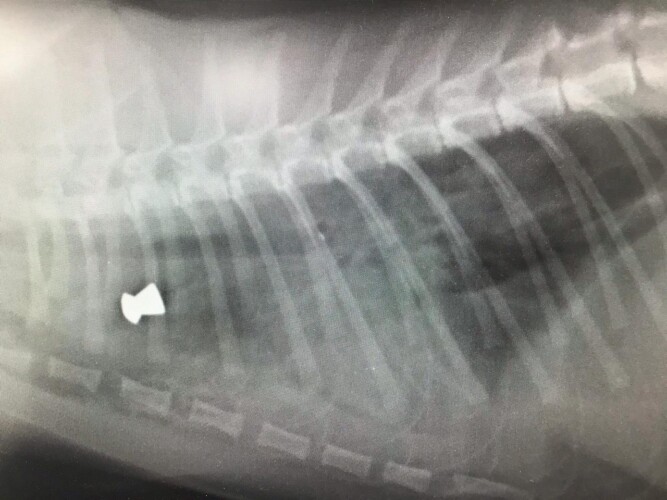

The kitten was later put down after being rushed to the vets having difficulty breathing, with the injuries being described as ‘unsurvivable’ after finding a bullet had gone through several organs.

Firearms experts analysed the x-ray to find the bullet was likely shot from a high-powered air rifle which has the ability to be silenced when fired.